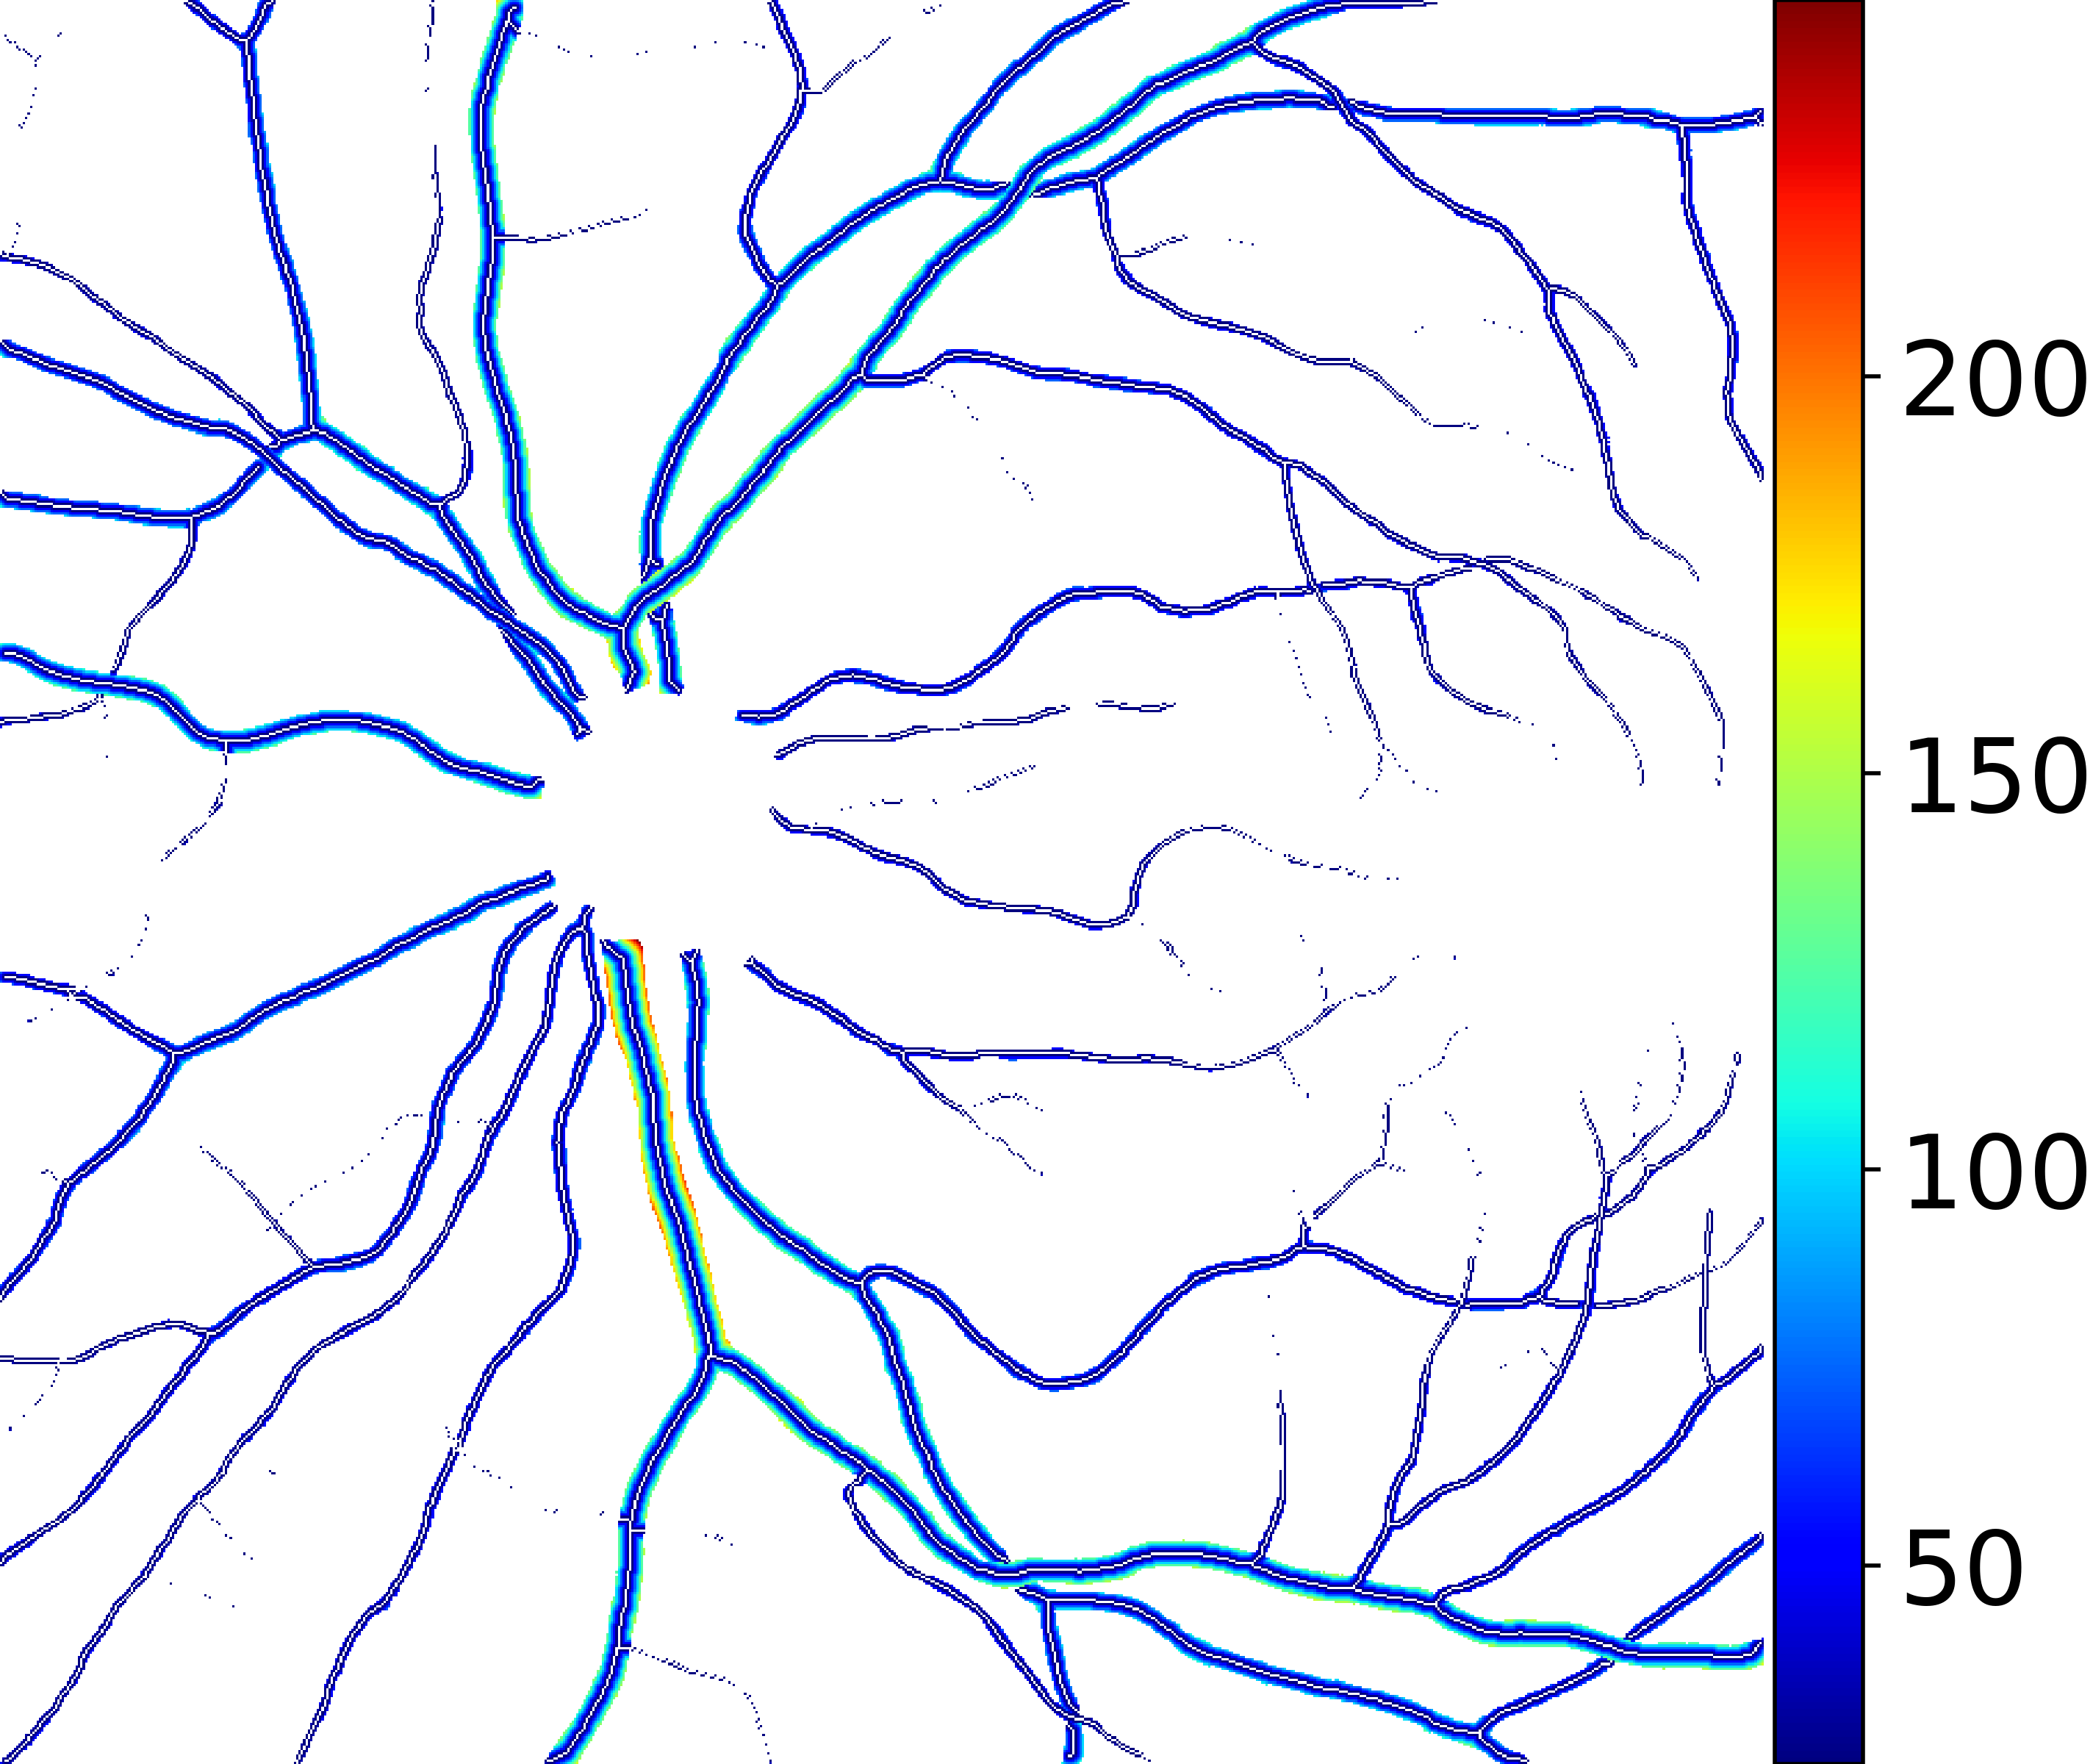

IV-C Vessel Width Estimation

From the segmentation predicted by the SegRAVIR network, our model measures the diameter of the arteries and veins. To this end, the segmentation probability map is first thresholded, using a constant value of 0.5, to obtain the medial curves of the vessels by iteratively identifying and removing border pixels while maintaining vessel connectivity, in an approach similar to the thinning algorithm presented by Zhang et al. [49]. Then, the distance transform of the medial curve mask is multiplied with the segmentation mask in a pixel-wise manner. The result is the diameter distance map with respect to the medial curves of the segmented vessels.

VI-B Vessel Width Estimation

Table VI presents a quantitative comparison of the measured diameters using the segmentation outputs of SegRAVIR and competing approaches. Using the pixel-wise annotated masks, the reference average diameter of the arteries and veins in the test set of the RAVIR dataset were measured as and , respectively. According to our analysis, SegRAVIR can accurately measure the diameter of the vessels and it achieves the smallest MAPE among the competing approaches. Specifically, in comparison to CE-Net, Iter-Net, and DU-Net, respectively, SegRAVIR is on average , and more accurate in terms of MAPE for the measured diameter of arteries and , and in terms of MAPE for the measured diameter of veins. Fig. 6 presents qualitative comparisons of reference and SegRAVIR estimated diameter maps.

(a) (b) (c)